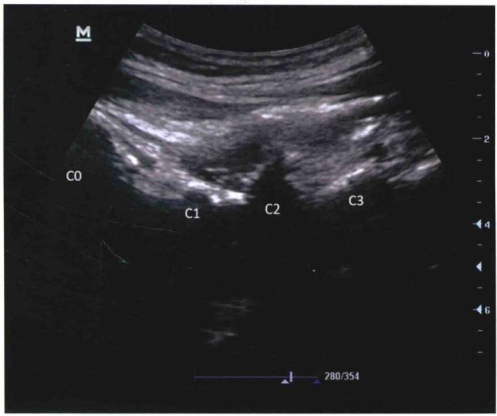

超声引导下穿刺分为外侧入路和后侧入路

采用平面内技术,在选定的穿刺点,以长3.5英寸带芯穿刺针在超声探头的下方以小关节为靶点从尾侧向头端方向进针( 图9和图10 )。

图9 / 超声引导下颈椎小关节内阻滞